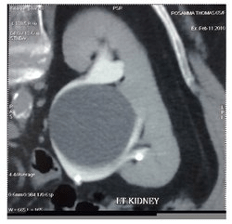

Name this pathology.

What is Transitional Cell Carcinoma (TCC)?